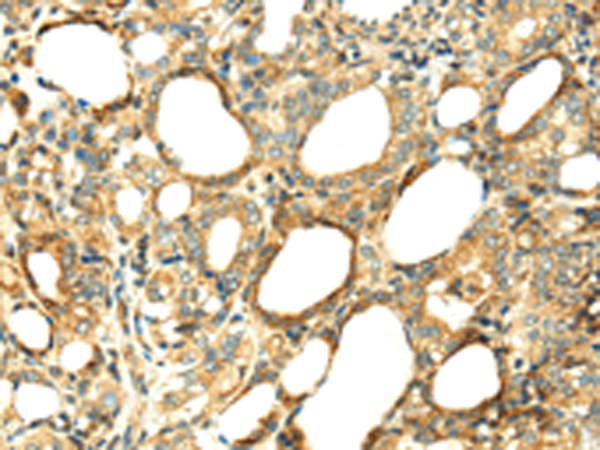

分类: 科研抗体货号: P08731别名: p6; CAGC; CGRP; MRP6; CAAF1; MRP-6; ENRAGE应用: IHC反应种属: Human

分类: 科研抗体货号: P08758别名: CAP; PI6; PTI; PI-6; SPI3; DFNB91; MSTP057应用: IHC反应种属: Human

分类: 科研抗体货号: P08757别名: OL-64应用: IHC反应种属: Human